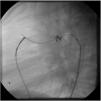

A coil was used in 139 patients (62.9%) and an Amplatzer duct occluder was used in 79 patients (35.7%). In the three remaining patients (1.4%), an Amplatzer vascular plug was used for closure (Figures 2-8). Despite the higher overall rate of coil device implantation, Amplatzer duct occluder usage had been clearly superior since 2011. Of all coil devices used, 55% were either 4x4 mm or 5x4 mm in size (Figure 9), and of all duct occluder devices used, 72% were Amplatzer duct occluder I 6x4 mm or 8x6 mm in size (Figure 10), which correlates to the fact that most patients who were referred had small- to moderate-sized ductus arteriosus. While ADO II and ADO II AS devices can be implanted in a retrograde fashion, only on two occasions was a retrograde deployment performed (both ADO II devices).

Both patients with history of previous PDA closure were successfully treated. The first was a seven year-old child who had a coil implanted at age three. The procedure was technically difficult, requiring a guidewire capture using a snare catheter to go through the residual PDA (Figure 11), and an Amplatzer duct occluder II 3x4 mm device was implanted successfully. The second patient was a 19 month-old child with PDA and pulmonary hypertension after an unsuccessful surgical ligation. In this case, sizing with a Tyshak balloon was required before implanting an Amplatzer duct occluder II 3x4 mm device (Figure 12).